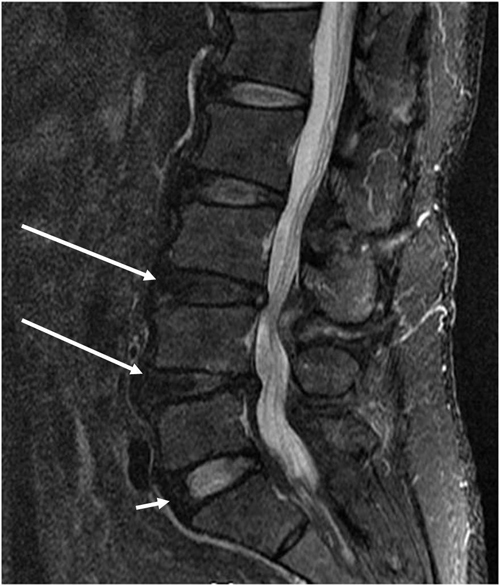

퇴행성 디스크 장애라고도 불리는 퇴행성 디스크 질환은 목이나 등 척추 디스크에 영향을 미치는 흔한 질환입니다. 그것은 디스크의 점진적인 마모를 특징으로 하며 통증, 불쾌감 및 제한된 이동성을 일으킵니다. 이 상태는 종종 노화와 관련이 있지만 부상이나 과다 사용의 결과로 발생하기도 합니다.많은 사람들에게 퇴행성 디스크 장애가 있다는 생각은 무섭고 압도적일 수 있습니다. 만성 통증에 대한 두려움과 이동성 상실은 쇠약해지고 불안, 슬픔, 좌절감을 일으킬 수 있습니다. 몸이 더 이상 예전처럼 기능하지 않는다는 사실을 받아들이기 어렵고 미래에는 많은 불편과 제한이 따를 수 있습니다.

퇴행성 디스크 질환이 더 진행될 경우 통증 관리가 필요할 수 있습니다. 여기에는 비스테로이드성 항염증제(NSAID)나 진통제 등 약물 사용이나 척추주사나 신경차단 등 기타 치료가 포함될 수 있습니다.심각한 경우 교정을 위해 수술이 필요할 수 있습니다. 문제. 외과적 선택에는 2개 이상의 척추뼈를 함께 융합하는 척추유합술과 영향을 받은 디스크를 제거하고 인공디스크로 교체하는 디스크가 포함됩니다. 이러한 절차는 통증을 줄이고 모빌리티를 개선하는 데 성공할 수 있지만 위험과 잠재적 합병증도 수반합니다.